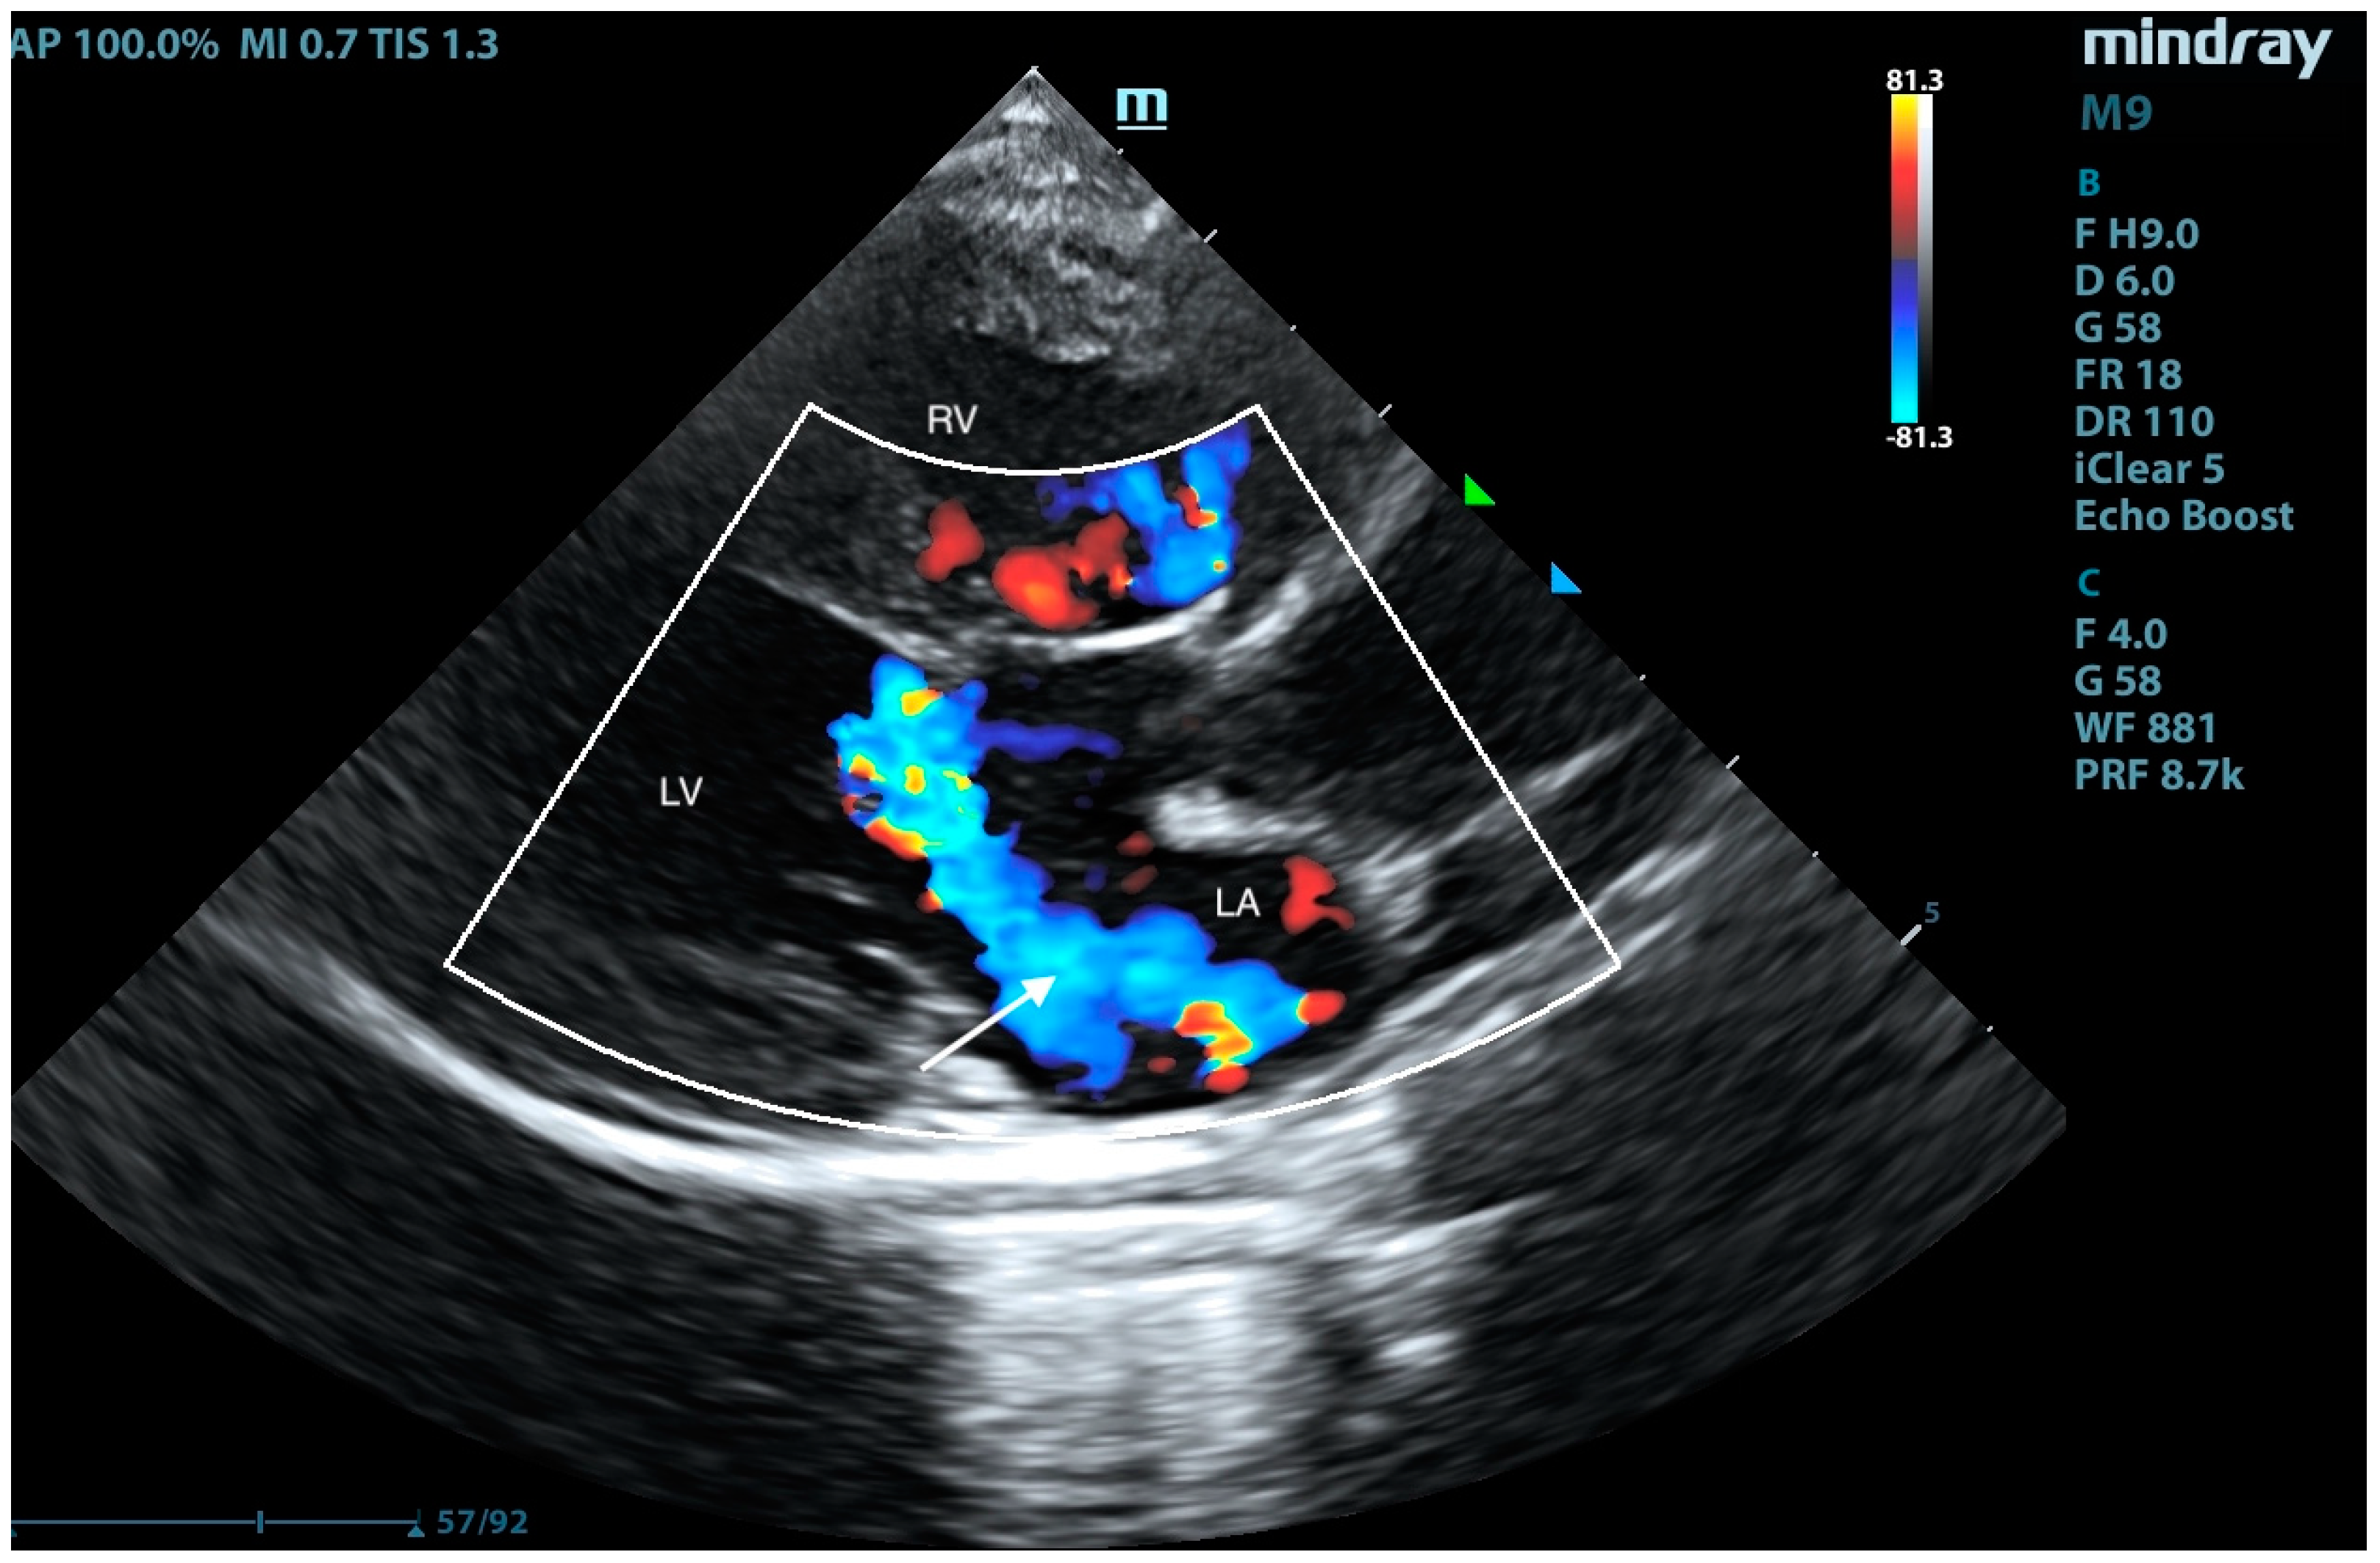

2. Case Presentation